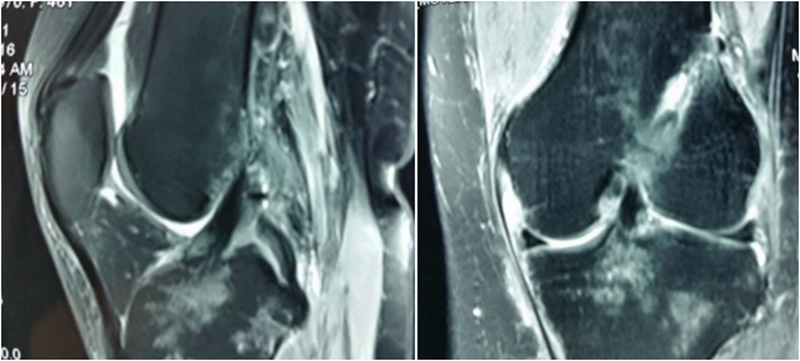

术前MRI

术后MRI

MRI检查评估ACL-R术后——韧带连续性信号好、方向好、愈合快,没有Cyclops综合征。